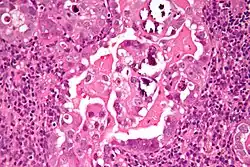

| Histology H&E of uterine serous papillary carcinoma. H&E stain. | |

Histopathologically, uterine serous carcinomas is typically characterized by (1) nipple-shaped structures (papillae) with fibrovascular cores (2) marked nuclear atypia (irregularities in the nuclear membrane, enlarged nuclear size), (3) psammoma bodies and (4) cilia. These are general findings in serous tumors which are also seen in such tumors in other anatomic locations.